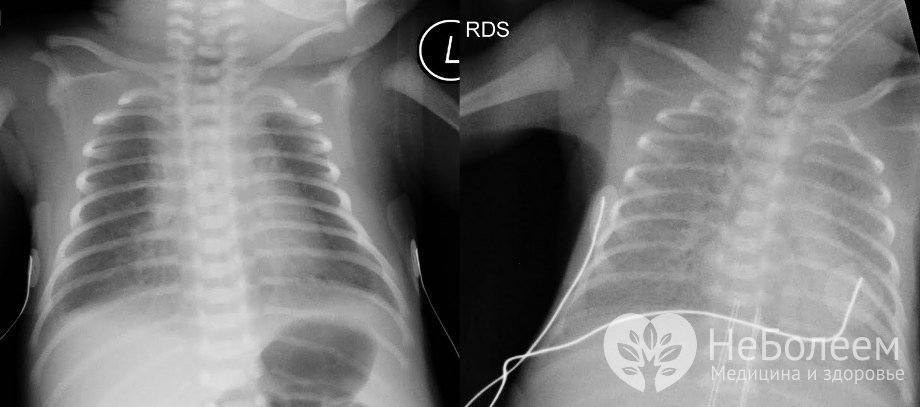

Пневмония у новорожденного на рентгеновском снимкеК основным причинам пневмонии у новорожденных относятся внутриутробное инфицирование, аспирация амниотической жидкости и слизи, нарушение кровообращения в легких, незрелость легочной ткани, спадение доли легкого, респираторный дистресс-синдром. Как правило, к развитию заболевания приводит не одна, а сочетание нескольких причин. Вирусно-бактериальная пневмония у новорожденных обычно возникает на фоне острых респираторных вирусных инфекций. Риск развития пневмонии у новорожденного повышается при наличии у беременной заболеваний, передающихся половым путем, лихорадке во время родов, развитии хориоамнионита, недонашивании беременности. Инфицирование ребенка может произойти при прохождении по родовым путям, в процессе кесарева сечения, и позже – в родильном отделении (госпитальная инфекция) или в домашних условиях.

Первичная диагностика пневмонии у новорожденных основывается на данных анамнеза и физикальной диагностики. В ходе аускультации отмечается укорочение перкуторного звука над пораженным участком легкого, усиление бронхофонии в той же области; физикальные изменения в легких асимметричны. Для подтверждения диагноза прибегают к рентгенографии грудной клетки – метод дает возможность определять инфильтративные изменения в легких, а также их локализацию и характер.

Для постановки диагноза пневмония у новорожденных проводят аускультацию и рентгенографию грудной клеткиИз методов лабораторной диагностики выполняют общий и биохимический анализ крови, бактериологические и серологические исследования.